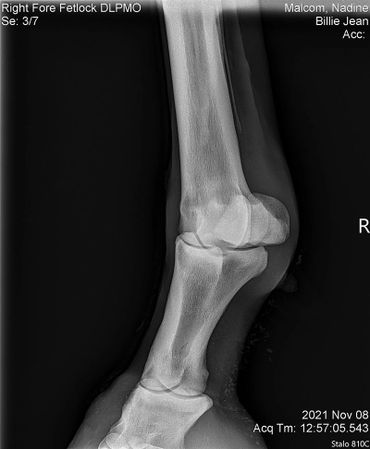

The only issue I'm still working on with her is that she still doesn't like to have a saddle put on her back. Once it's on she's good to go. I've had this mare checked for everything! She got scoped for ulcers, checked for kissing spine, her knees x-rayed since she's a little over the knee and her coffin/ fetlock x-rayed. She's totally fine! I assume that this poor girl was probably ridden in a really poor fitting saddle for years which brought her great uncomfort. I believe over time she will eventually get over this but I can't stress enough that patience is required while saddling her!

BJ also had hr knees, fetlock and coffin joint x-rayed on July 7, 2022. Her vet bill was $185.

We did a full wellness and lameness exam and everything looked pretty good. She showed some soreness in her right front fetlock so we did some x-rays but nothing really to see that would raise concern. We also did x-rays on her stomach and it showed she has some sand which we have been treating with Sand Clear.We didn't do x-rays on her knees. Dr. Johnson said she's probably got some fluid in there because it looks like she used to hit her knees on something a lot so we are rubbing some DMSO on it to relieve some of the swelling.Billie Jean also got a dental float. After examining her teeth closer it turns out she is more like 18-20 years old.